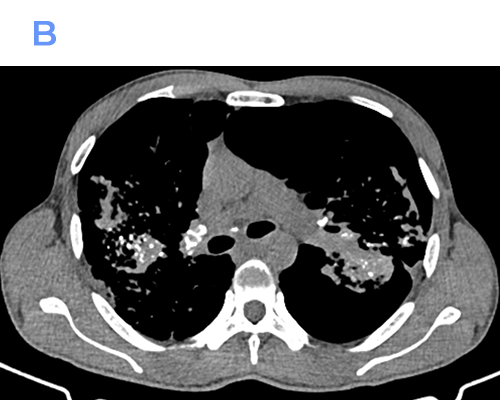

Computed Tomography (CT)

• Numerous well-defined centrilobular and perilymphatic nodules in the upper lobes.

• Conglomerate fibrotic masses with irregular margins and variable internal calcification.

• Traction bronchiectasis and bronchiolectasis adjacent to fibrotic areas.

• Marked architectural distortion with posterior and superior displacement of fissures.

• Enlarged hilar and mediastinal lymph nodes, frequently showing peripheral (“eggshell”) calcification.

• Areas of emphysema, especially adjacent to fibrotic masses.

CT is superior in detecting early PMF, subtle nodal calcifications, and complications such as superimposed infection or lung cancer.